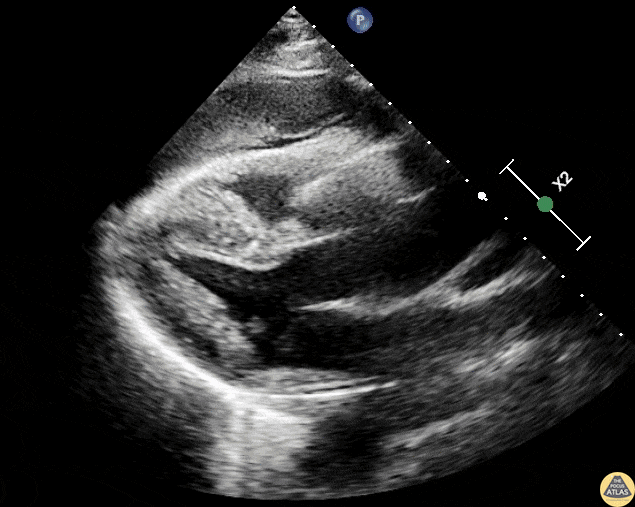

Thoracic Aortic Dissection & Aneurysm - Ascending Aortic Aneurysm with Dissection Flap

48 y/o male presents with chest pain for >24 hours. Parasternal Long Axis demonstrates ascending aortic aneurysm with a dissection flap and hemorrhagic pericardial effusion. Patient was transferred to ICU in shock. Contributors: Dr. Adriana Brentegani (@dribrentegani) Hospital das Clínicas da Faculdade de Medicina da Universidade de São Paulo - São Paulo, Brasil